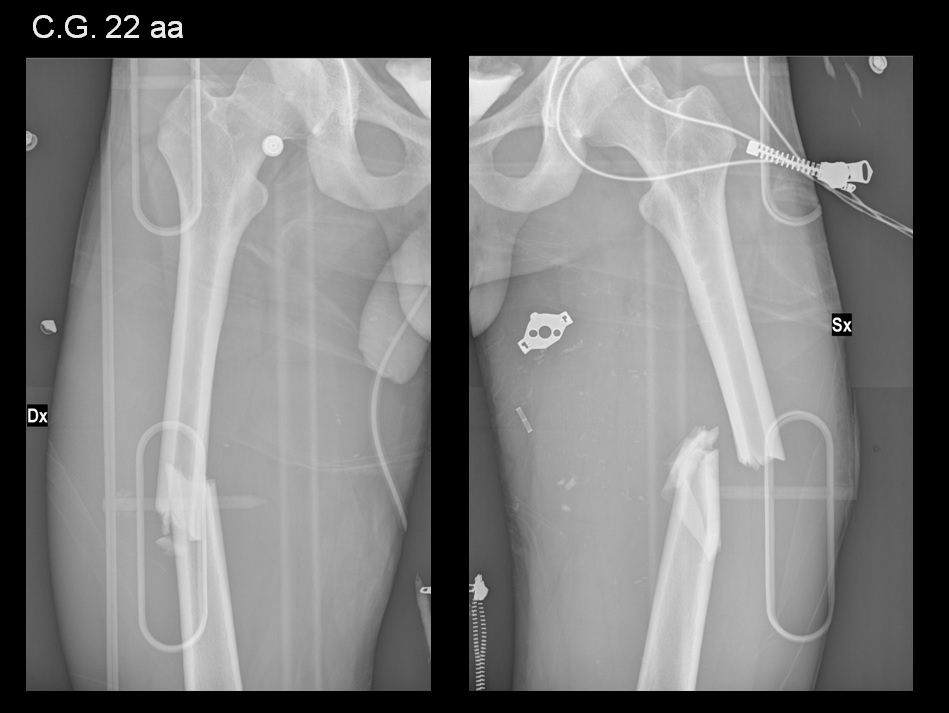

La frattura sovracondiloidea di femore rappresenta un evento grave sia per la prognosi che per il tipo di trattamento necessario.la le fratture sovracondiloidee del femore sono di grande frequenza. E' stata sottoposta ad un intervento.